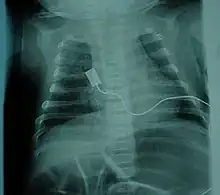

The respiratory system is the most common system to be affected and the complications are the leading cause of death in SMA types 0/1 and 2. SMA type 3 can have similar respiratory problems, but it is more rare.[24] Complications arise due to weakened intercostal muscles because of the lack of stimulation from the nerve. The diaphragm is less affected than the intercostal muscles.[24] Once weakened, the muscles never fully recover the same functional capacity to help in breathing and coughing as well as other functions. Therefore, breathing is more difficult and pose a risk of not getting enough oxygen/shallow breathing and insufficient clearance of airway secretions. These issues more commonly occur while asleep, when muscles are more relaxed. Swallowing muscles in the pharynx can be affected, leading to aspiration coupled with a poor coughing mechanism increases the likelihood of infection/pneumonia.[59] Mobilizing and clearing secretions involve manual or mechanical chest physiotherapy with postural drainage, and manual or mechanical cough assistance device. To assist in breathing, Non-invasive ventilation (BiPAP) is frequently used and tracheostomy may be sometimes performed in more severe cases;[60] both methods of ventilation prolong survival to a comparable degree, although tracheostomy prevents speech development.[61]